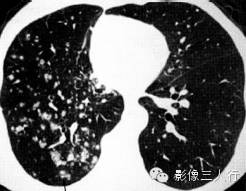

| 病毒性肺炎(图1) | 粟粒性肺结核(图2) | 细支气管肺泡癌(图3) | 肺尘埃沉着病(图4) | 肺泡蛋白沉着症(图5) | 血吸虫病(图6) | |

散在分布,6〜8mm或更小 | 分布均匀,直径1〜2mm | 分布不均,直径6〜7 mm | 分布不均,直径多为2〜5mm | 地图样、铺路石征 | 大小不等,直径多为1〜5mm |

较模糊 | 较清楚或较模糊 | 较清楚 | 较清楚 | 较清楚 | 较模糊 |

病灶密度相同,大小不等 | 病灶密度相同或不同 | 病灶密度相同,呈含气支气管征及蜂窝征 | 病灶密度不均,有钙化 | 磨玻璃密度,地图样分布和铺路石征 | 病灶密度不均,典型者可见晕征 |